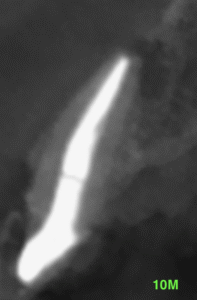

PA(2025.1.16)

#7,10はほぼ治療がなされていない。再根管治療が必要な案件だ。

CBCT(2025.1.16)

#7

頬側皮質骨が消失している。

これが圧痛の原因だろう。

#10

#10も#7に同じである。

根管形成・当該部位への根管充填がほぼなされていないように見えることから, 再根管治療へ移行した。